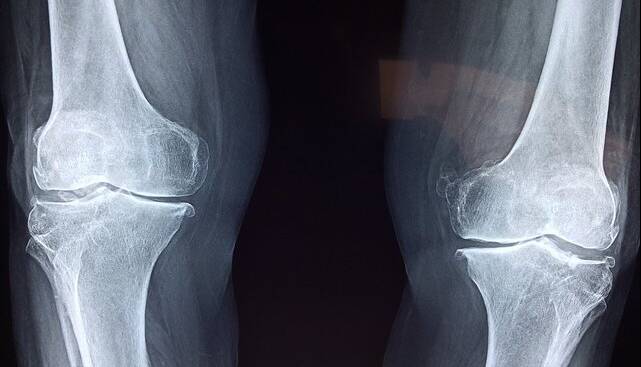

ایسنا/ محققان یک سیستم تشخیصی مبتنی بر هوش مصنوعی توسعه دادهاند که میتواند تراکم مواد معدنی استخوان را هم در ستون فقرات کمر و هم در استخوان ران پا، بر اساس تصاویر اشعه ایکس تخمین بزند.

در مجموع ۱۴۵۴ تصویر اشعه ایکس با استفاده از سیستم دانشمندان مورد تجزیه و تحلیل قرار گرفت. میزان حساسیت عملکرد برای کمر و استخوان ران بیماران مبتلا به کاهش تراکم استخوان به ترتیب ۸۶.۴ و ۸۴.۱ درصد بود.

به نقل از مدیکالاکسپرس، میزان اختصاصی بودن آن نیز ۸۰.۴ و ۷۶.۳ درصد بود. حساسیت، توانایی آزمایش در شناسایی صحیح افراد مبتلا به پوکی را نشان میداد در حالی که اختصاصی بودن، توانایی آن را در شناسایی صحیح افراد بدون پوکی استخوان نشان میداد. این آزمایش همچنین از حساسیت و اختصاصی بودن بالایی برای دستهبندی بیماران مبتلا به پوکی استخوان و بدون آن برخوردار بود.

دکتر تورو مورو، نویسنده مسئول این مقاله از دانشگاه توکیو، میگوید: اندازهگیری تراکم مواد معدنی استخوان برای غربالگری و تشخیص پوکی استخوان ضروری است، اما دسترسی محدود به تجهیزات تشخیصی به این معنی است که میلیونها نفر در سراسر جهان ممکن است از این بیماری بیاطلاع بمانند.

این سیستم هوش مصنوعی پتانسیل تبدیل عکسهای رادیولوژی بالینی معمول را به ابزاری قدرتمند برای غربالگری دارد و امکان تشخیص زودهنگام، گستردهتر و کارآمدتر پوکی استخوان را فراهم میکند.